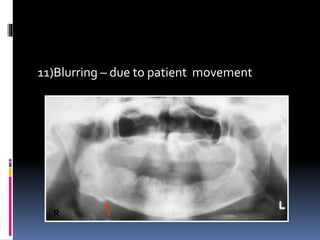

11)Blurring – due to patient movement